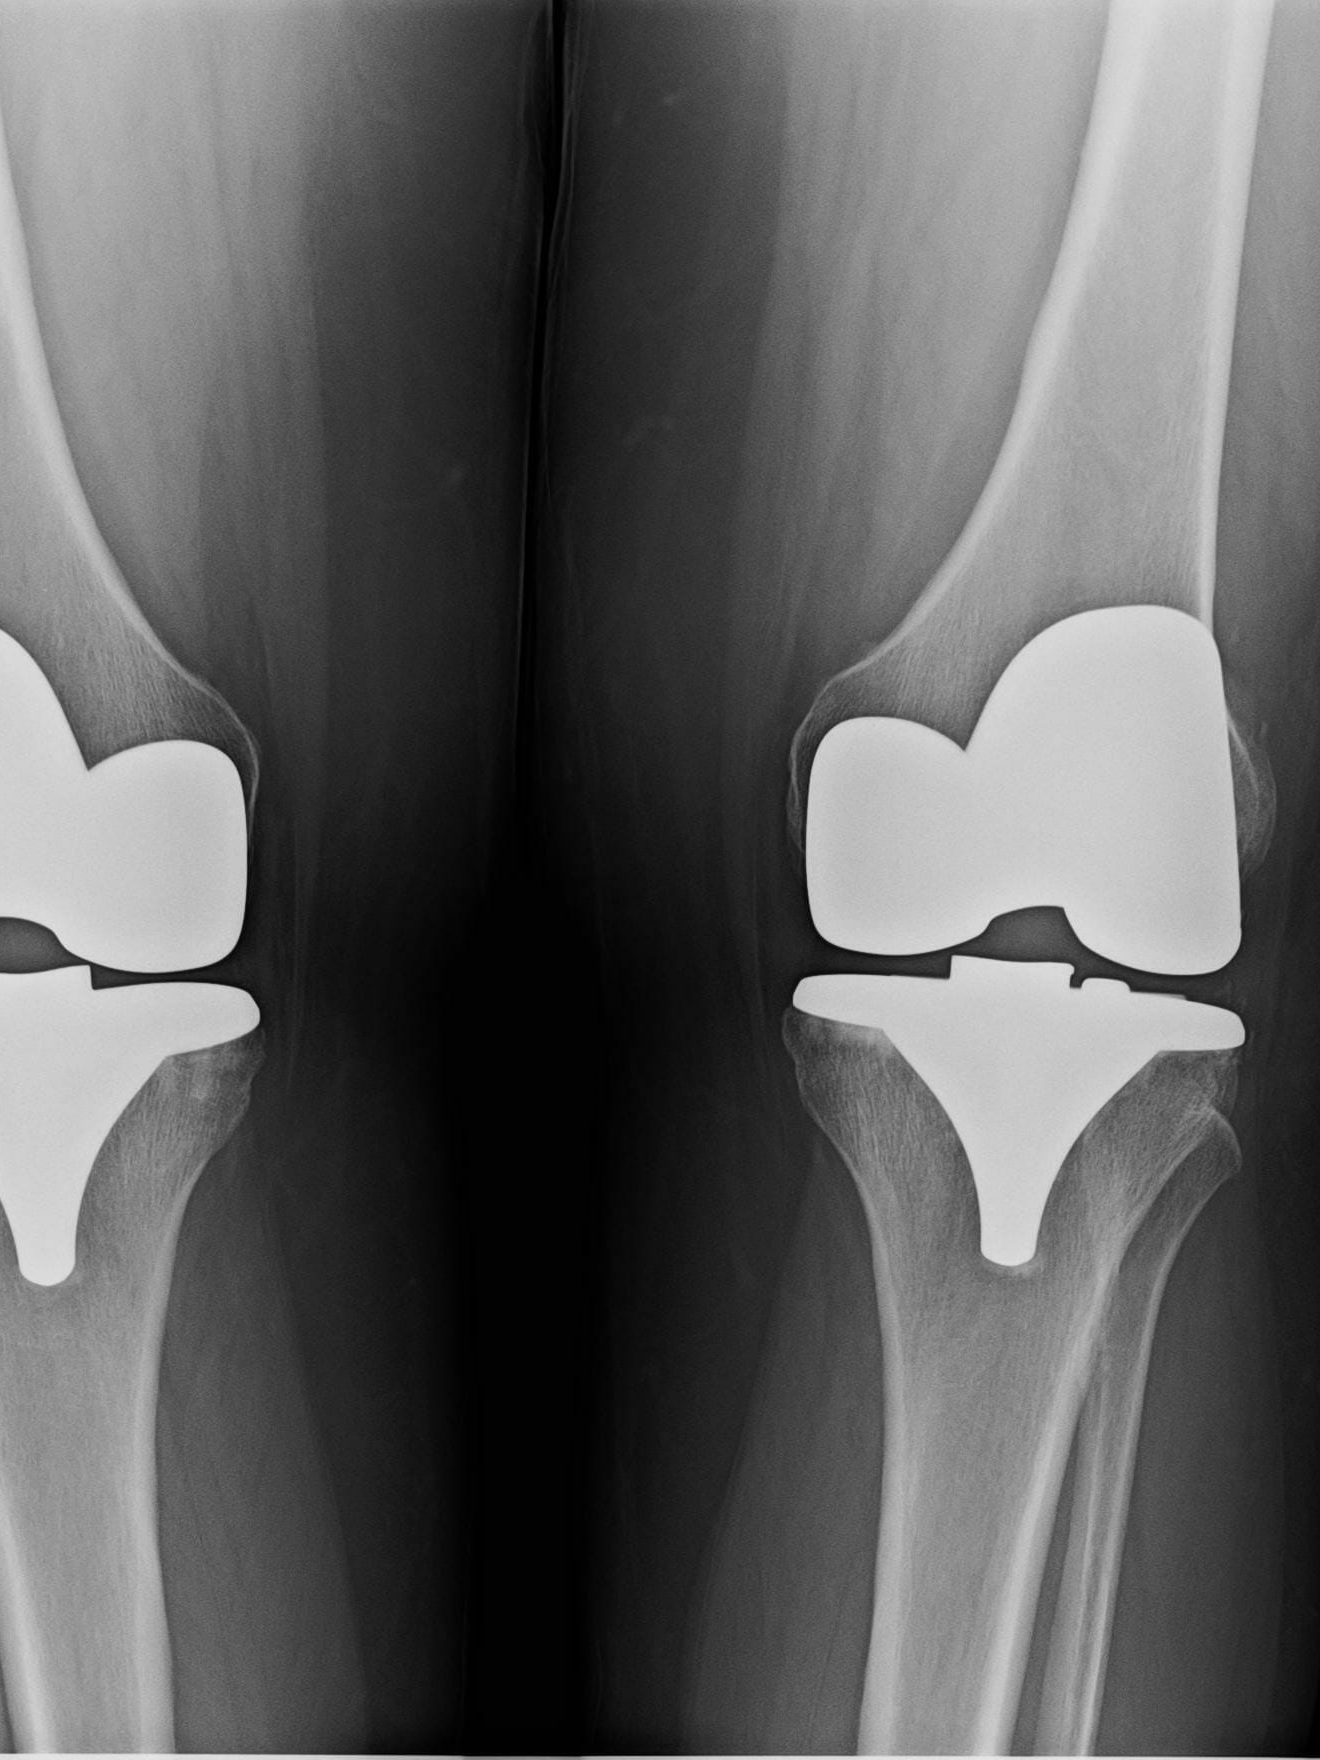

Kevin’s Bilateral Knee Replacement and Recovery

Bilateral Knee Replacement and Recovery and golf in the spring. Now that’s a bilateral knee replacement story you want to hear.

In this episode of The Bee’s Knees Podcast, we delve into the inspiring recovery journey of Kevin, who has experienced bilateral knee replacement surgery within a brief timeframe. At 64 years old, Kevin shares the challenges he faced due to chronic knee arthritis for nearly eight years, which ultimately led him to decide on surgeries for both knees—first in late August and then just 11 weeks later.